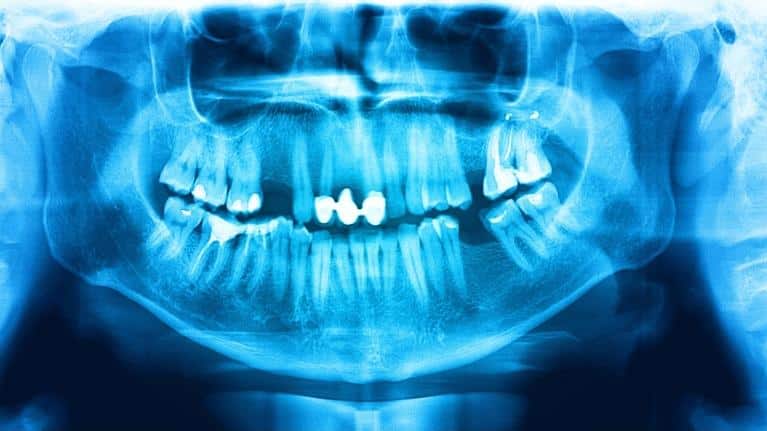

Your dentist in Southeast, TX is often the first who will notice a suspicious lesion that requires a biopsy. Oral cancer lesions vary in color from white to black or red and can be raised, smooth, or even concave.

When you choose Nederland Family Dental as your dentist in Southeast, TX, you have had an oral cancer screening, though you might not be aware of it. Your hygienist or Dr. Gomez will often feel your neck to check the thyroid, use a piece of gauze to grab the tongue and look at the sides and underneath, feel the gums for lumps or cysts, and have a look at the back of the throat to identify any lesions that cause concern.